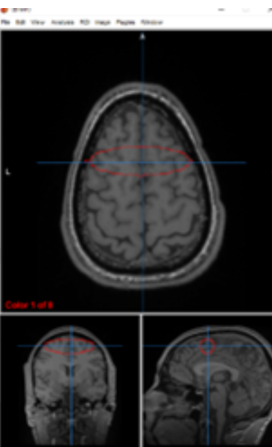

lateral ventricles

circulate and produce cerebrospinal fluid